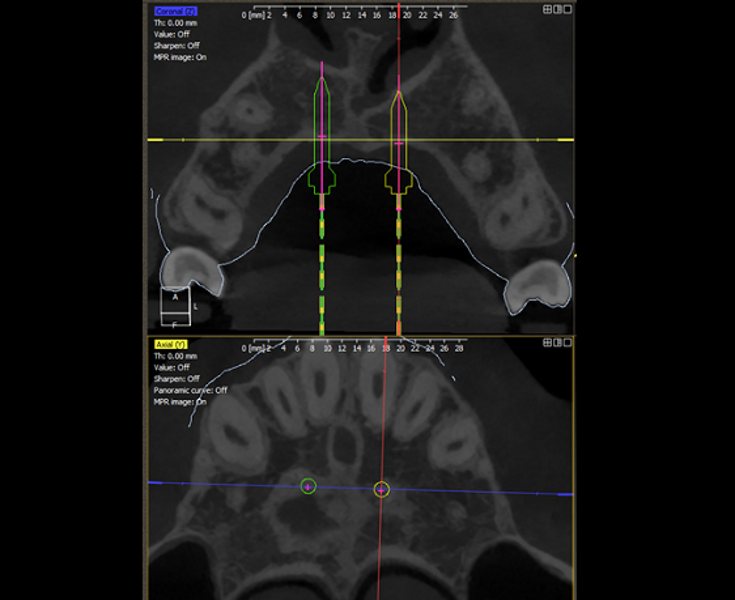

DDS-Pro enables precise planning, guided implantation and appliance design in orthodontics by integrating CBCT data and intra-oral scans into a streamlined digital workflow. (All images: Polorto)

1. capture and analysis of the CBCT scan and intra-oral scan to determine optimal mini-implant placement in line with anchorage needs and appliance design;

2. creation of surgical guides for precise implantation;

DDS-Pro software (Polorto) supports both the two-stage and single-stage approaches. However, the single-stage method eliminates implant position discrepancies commonly encountered in the two-stage workflow. It also significantly enhances installation accuracy, improving reproducibility and eliminating the need for additional appointments or chairside adjustments.

Once 3D planning has been completed, mini-implants can be placed with high precision, independent of the operator’s manual skill. The appliance, anchored to these implants, functions exactly as designed.